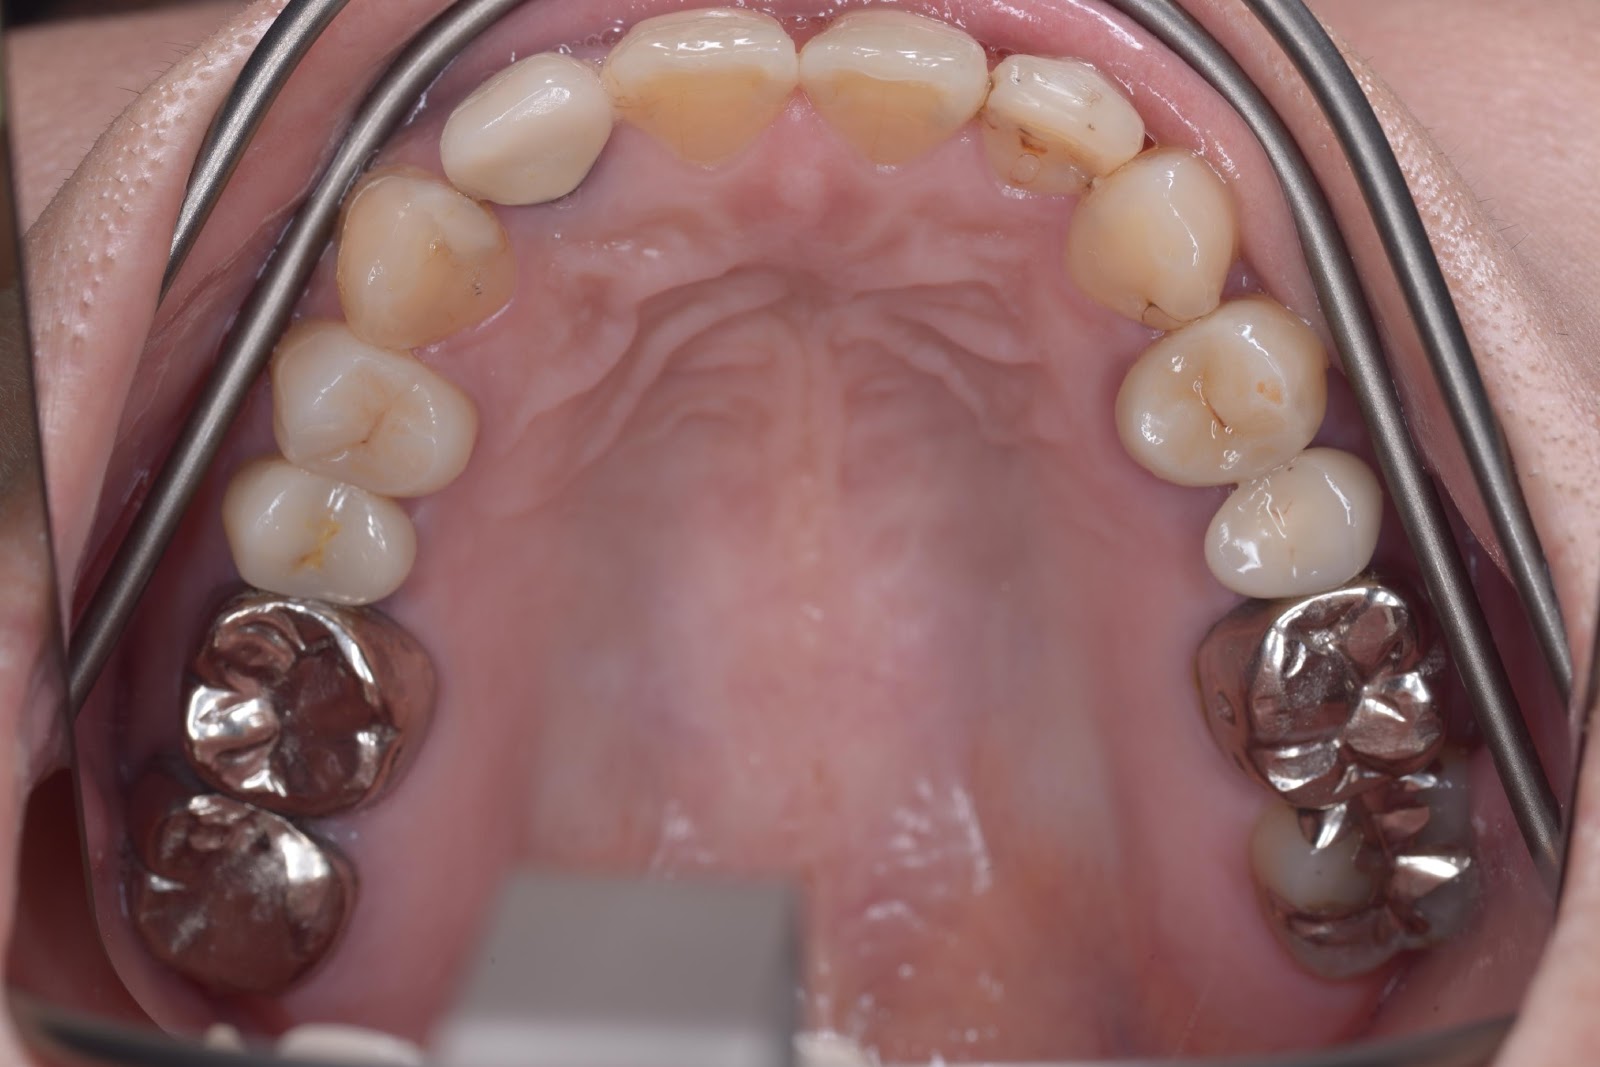

初診時

CASE-1左上の小臼歯部 インプラント埋入 1本

50代 女性